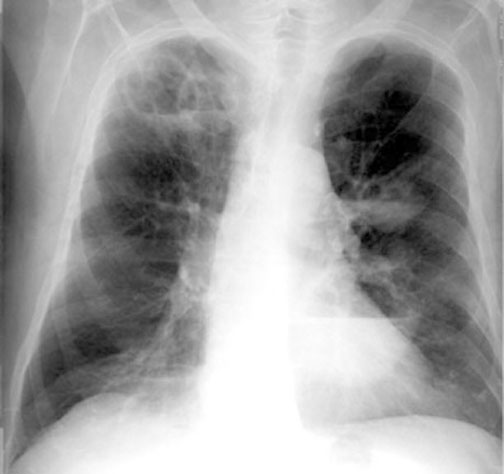

Case 1 Labeled Image What are the conditions where you get thin walled cavities?